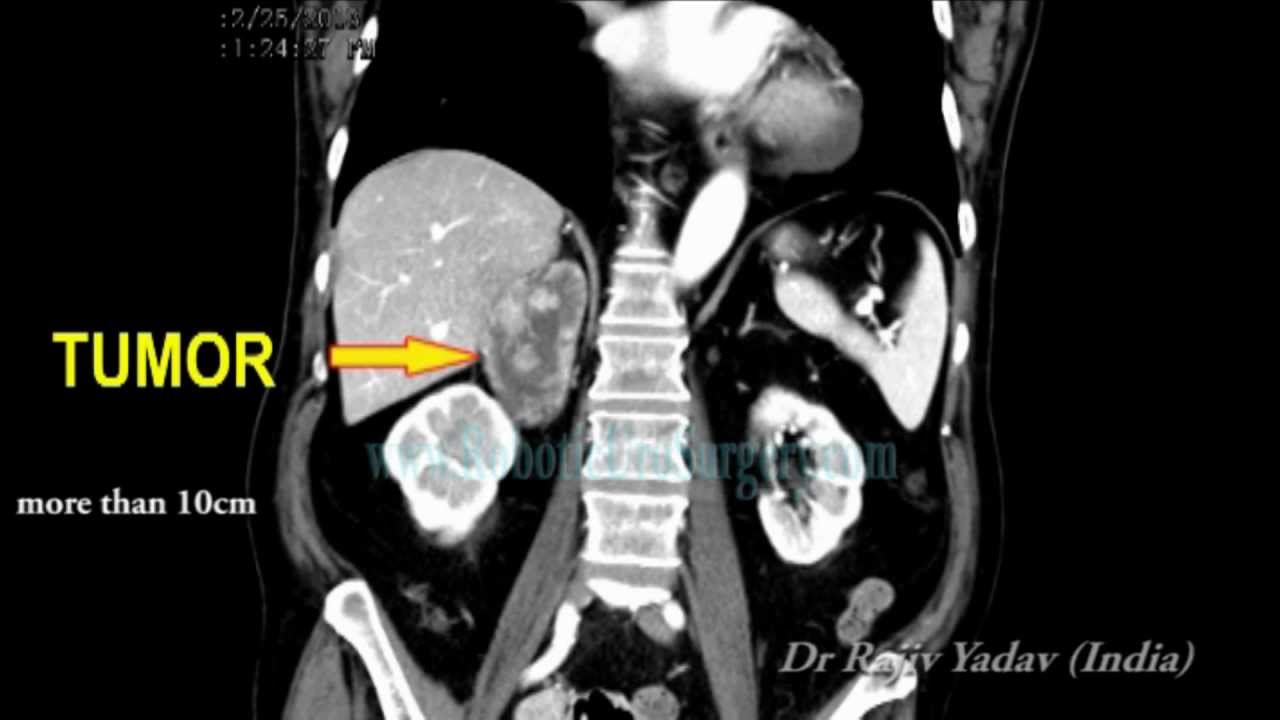

From www.youtube.com

Adrenal cortical cancer_Cancer Surgery in India YouTube Adrenal Cortical Cancer Survival Rate Adrenal tumors are found in about 1 in every 10 people who have an imaging test (like a ct or. Because there are so few people with acc,. Doctors estimate acc survival rates by how groups of people with acc have done in the past. How common are adrenal cancers? The majority of patients with acc present with advanced disease. Adrenal Cortical Cancer Survival Rate.